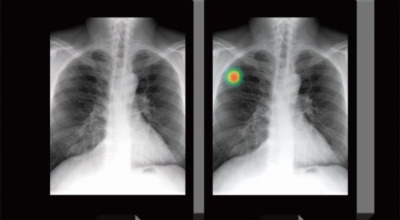

폐암은 폐에 생기는 악성 종양을 말합니다. 폐에서 직접 발생하는 원발성 폐암과, 다른 장기에서 전이되어 온 전이성 폐암으로 나눌 수 있어요. 전 세계적으로 매년 약 130만 명이 폐암으로 사망하는데, 이는 암으로 인한 사망 원인 중 가장 높은 비중을 차지하고 있습니다.

폐암 초기증상

폐암 초기증상 ② 기침

기침은 폐암 초기 증상 중 가장 흔하게 나타나는 증상입니다. 폐암 환자의 약 75%가 잦은 기침을 겪는데, 감기와 구분이 어려워 대수롭지 않게 넘기는 경우가 많으니 주의가 필요합니다. 따라서 기침이 오랜 시간 지속된다면 꼭 진찰을 받아보시길 권합니다.